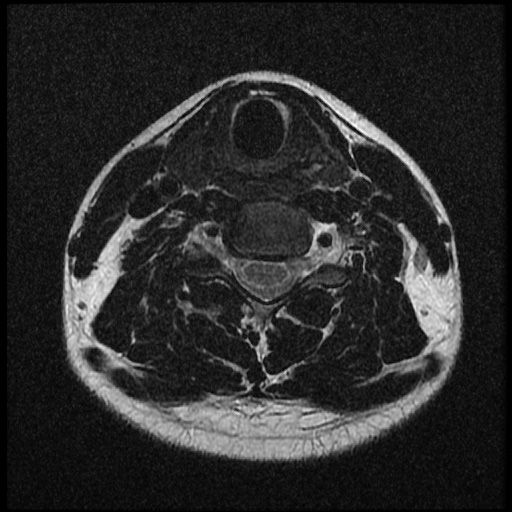

이 MRI 사진은 21년도 사고 당시 찍은 MRI 사진 입니다. 확인 부탁드립니다~

전체 mri를 다 봐여겠지만 보여주신 mri 컷에서는 의미있는 경추 디스크탈출이 보이지 않습니다.